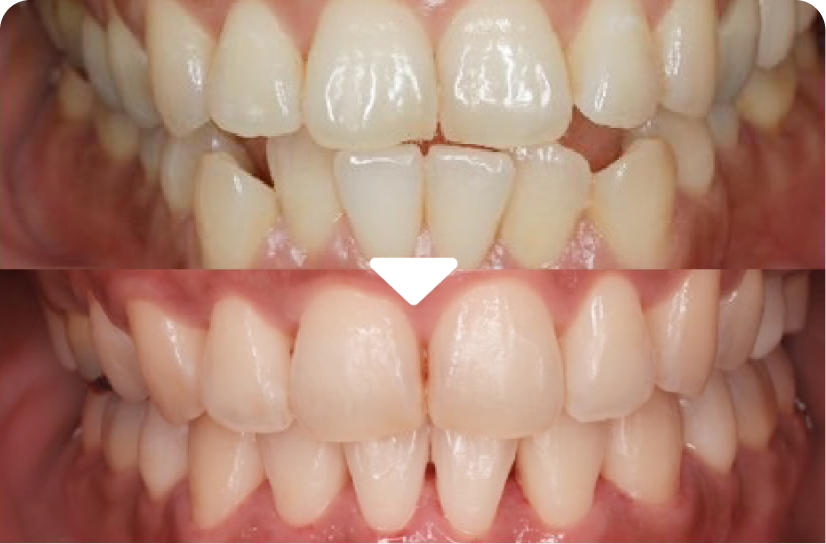

奥歯の審美修復治療

右上6、7にセメント治療がされていましたが、むし歯の再発があり形態も不適合でした。むし歯の部分のみ最小限に削りコンポジットレジン(CR)を使って再度修復しています。自然な色に合わせて修復し周りの歯と見た目が自然に馴染むようにしています。